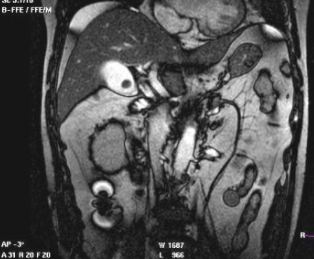

膽囊結石的CT表現:

CT的密度分辨率高,更有利于膽結石的發現。膽石的CT表現與其化學成分密切相關,其CT值與膽固醇含量呈負相關,與膽紅素和鈣含量呈正相關。

CT表現主要有:高密度結石(均勻或不均勻);略高密度結石;等密度結石,與膽汁密度相等平掃不易區分;低密度結石;環狀結石。